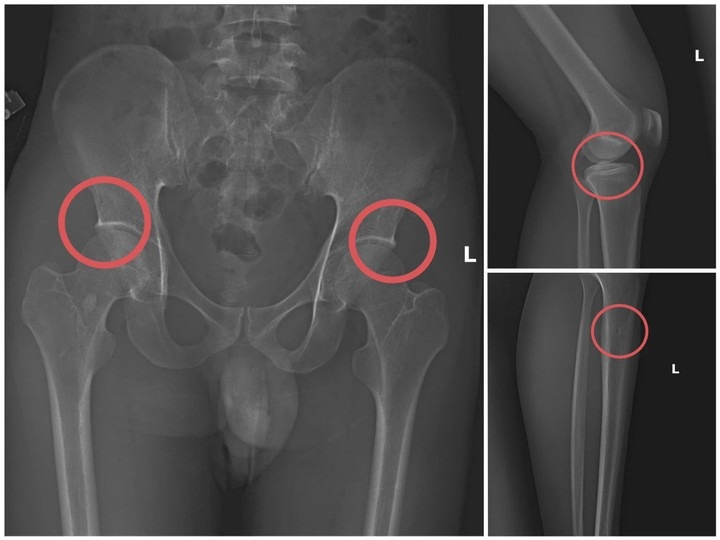

| Bản phim chụp XQ một số tổn thương xương do đối tượng tạo ra. Ảnh: Công an tỉnh Phú Thọ. |